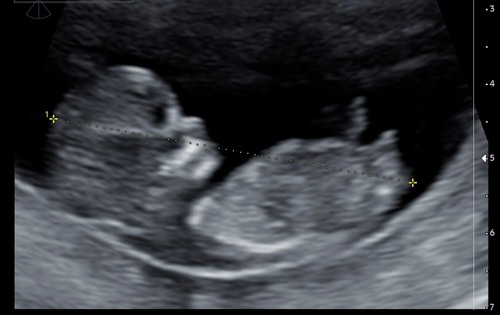

Dit is misschien een betere foto. Iemand een idee?

De nub is hier wel heel duidelijk, maar het is nog erg vroeg, het kan alle kanten nog op gaan. ik zeg 60% 馃挆

Ik denk niet dat wat je ziet de nub is. Ik denk eerder de navelstreng die recht naar beneden loopt. Je ziet namelijk dat hij begint ter hoogte van de navel en eindigt voor het uiteinde van de billetjes.